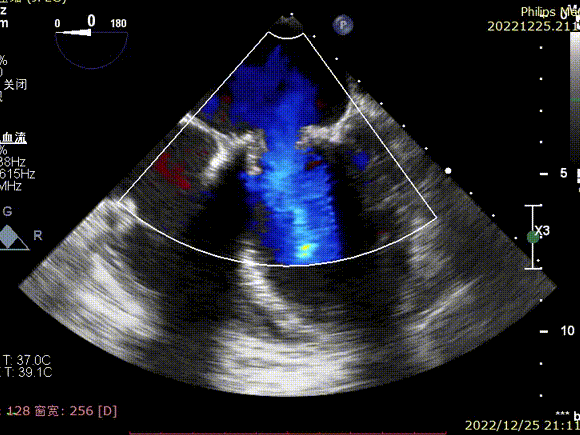

术前TEE显示大量反流